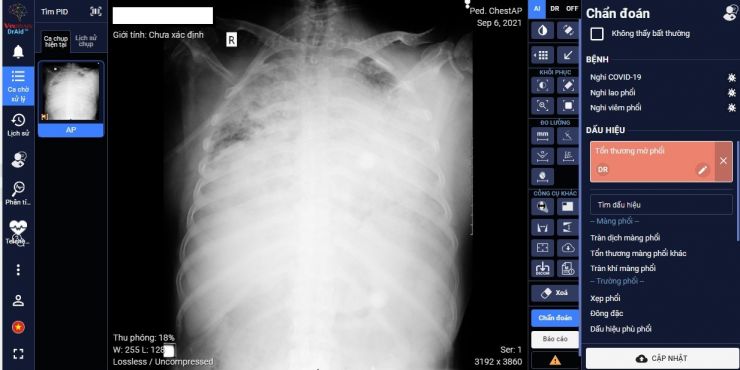

Các bệnh nhân đến Bệnh viện sẽ được thực hiện chụp X-quang ngực định kỳ trong thời gian đến khám và điều trị thì phần mềm trí tuệ nhân tạo AI sẽ hỗ trợ cho các bác sĩ lâm sàng việc chẩn đoán bệnh và giúp tiên lượng tình trạng bệnh tốt hơn hoặc xấu đi dựa trên việc khoanh vùng tiến triển các tổn thương trên phim phổi. Các quy trình chụp Xquang ngực được đảm bảo nguyên tắc kiểm soát nhiễm khuẩn và không để lây lan mầm bệnh Covid-19.

Điều này sẽ giúp các bác sĩ điều trị kịp thời có phương án ưu tiên xử lý các trường hợp có tiên lượng xấu (ngay cả khi không có biểu hiện các triệu chứng bất thường bên ngoài) nhằm giảm thấp tử vong của người bệnh.

Từ ngày 02 tháng 6 năm 2021 đến nay, tổng số 5.537 ca chụp X-quang tại Bệnh viện với ứng dụng phần mềm AI. Tất cả các ca phân tích trên phần mềm trí tuệ nhân tạo đều phù hợp đến hơn 99% so với chẩn đoán của bác sĩ chuyên khoa Xquang. Kết quả phân tích như sau:

- 2.341 ca chẩn đoán bệnh Covid-19 chiếm tỉ lệ 42,3%.

- 86 ca nghi nhiễm Covid-19 chiếm tỉ lệ 1,6%.

- 1.148 ca có bất thường về của tim, phổi và màng phổi khác cũng như các thiết bị y tế trên lồng ngực chiếm tỉ lệ 20,7%.

- 1.962 ca bình thường chiếm tỉ lệ 35,4%.

Chụp Xquang kỹ thuật số có sử dụng phần mềm ứng dụng trí tuệ nhân tạo (AI) trong hỗ trợ chẩn đoán, tiên lượng bệnh nhân Covid-19 trong giai đoạn hiện nay có ý nghĩa thực tiễn, khoa học, hiện đại và có tính chính xác rất cao. Từ đó mang ý nghĩa kinh tế và xã hội to lớn vì giúp giảm chi phí, đưa ra cảnh báo chính xác nguy cơ mắc bệnh Covid-19, từ đó giúp giảm nguy cơ lây nhiễm cộng đồng và hỗ trợ giảm thấp tỉ lệ tử vong khi được điều trị đúng và kịp thời